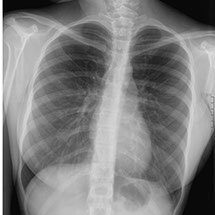

Elle peut être réalisée sur tout le corps et permet avant tout l’étude des os,

Pour les poumons : des infections, la tuberculose, des tumeurs

Elle utilise les rayons X, consistant à impressionner un film qui sera plus ou moins noirci selon l’organe radiographié : ainsi les os apparaîtront blancs et l’air noir ; les tissus mous seront de différentes nuances de gris.

Dans notre cabinet, la technique est numérisée et la surface sensible est en fait un capteur et non un film, ce qui permet de modifier le contraste après avoir pris le cliché et d’agrandir certaines zones pour mieux voir.